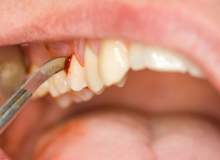

Romatizmalı Hastalar Da Hamile Kalabilir

Hacettepe Üniversitesi Öğretim Üyesi Prof. Dr. Ertenli: Romatizmalı hastaların da hem tedavi olmaya hem gebe kalmaya, çocuk doğurmaya ve çocuklarını emzirmeye hakları vardır. Bunun için hem gebelik hem de süt verme döneminde kullanılabilecek ilaçlar